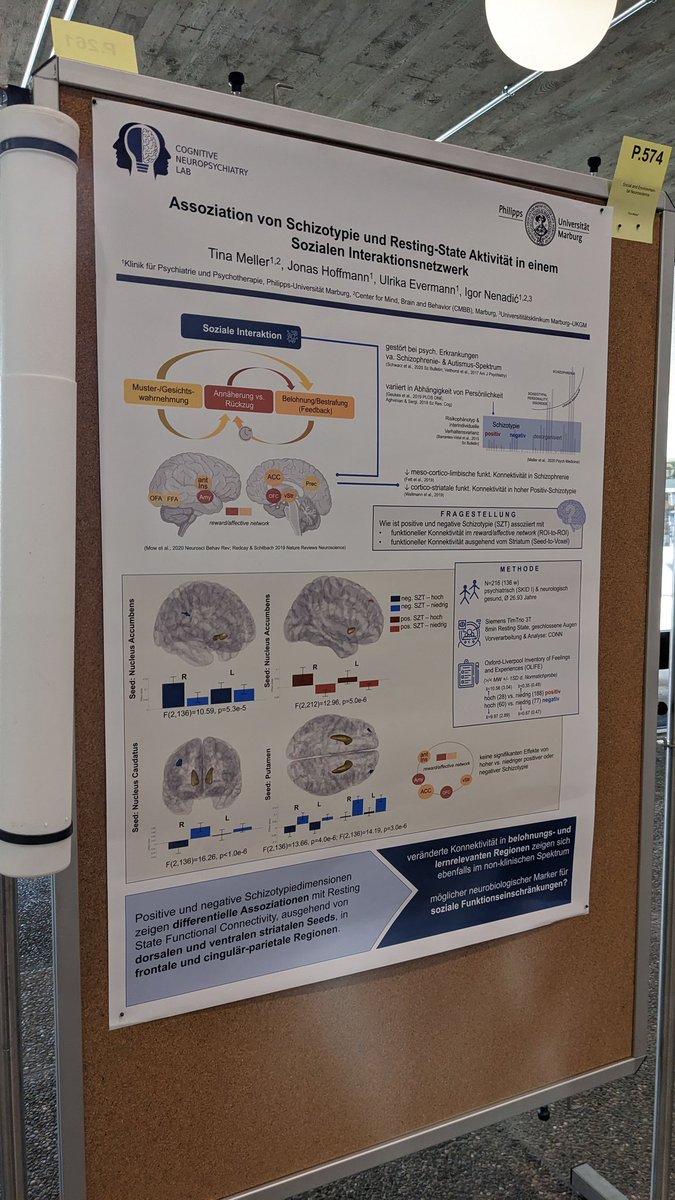

Ahhh this is so cool 🎉🎉🎉 Im so excited for those two Dr. Katharina Brosch Frederike Stein and thrilled to be a part of it #paperthread ⬇️

Super excited to share our molecularpsychiatry paper on shared GMV alterations across MDD, BD, and SSD🥳. Loved working with Dr. Katharina Brosch and all other colleagues of #FOR2107. Results below ⬇️ #ScienceTwitter #neuroscience